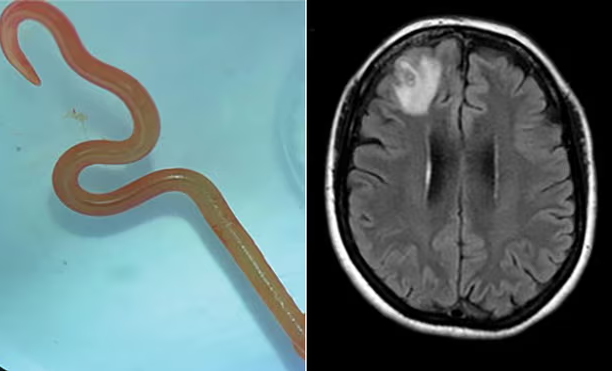

خاتون کے دماغ کے سکین کے بعد کیڑے کی ڈی این اے ٹیسٹنگ سے شناخت ہوئی (فوٹو: کینبیرا ہیلتھ)

نیورو سرجن ڈاکٹر ہری پریا بندی نے اپنی مریضہ کے دماغ سے آٹھ سینٹی میٹر لمبا طفیلی (پیراسائیٹ) راؤنڈ ورم نکالا تھا اور وہ ڈاکٹر سنجے سیننائیک اور ہسپتال کے دیگر ساتھیوں سے مشورہ کرنا چاہتی تھیں۔

یہ دراصل راؤنڈ وارم تھا جسے اوفیڈاسکیریز رابرٹسی کہا جاتا ہے اور جس کے بارے میں محققین کا کہنا ہے کہ یہ کینگروز اور سانپوں کی ایک قسم پائیتھون میں پایا جاتا ہے تاہم انسانوں میں نہیں۔

خاتون کے دماغ کے سکین کے بعد اس کیڑے کی ڈی این اے ٹیسٹنگ سے شناخت ہوئی۔